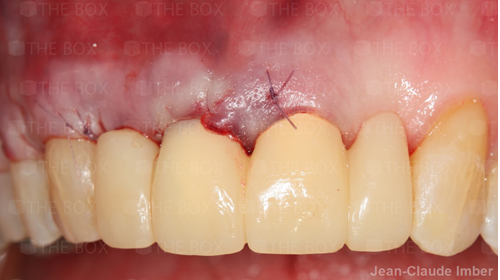

A new case was made public by Jean-Claude Imber check it out here.